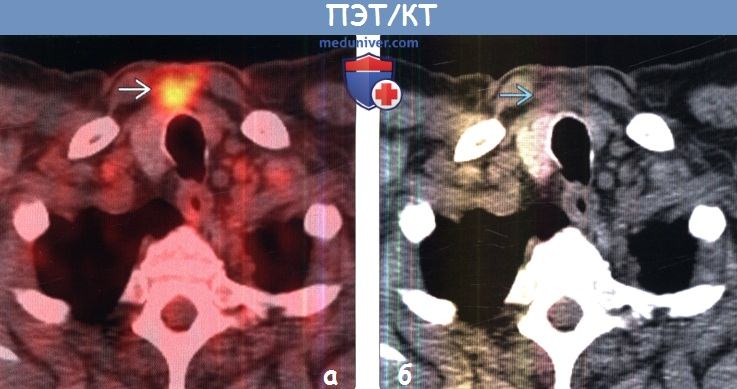

Диагностика лимфомы Ходжкина с помощью ПЭТ и КТ